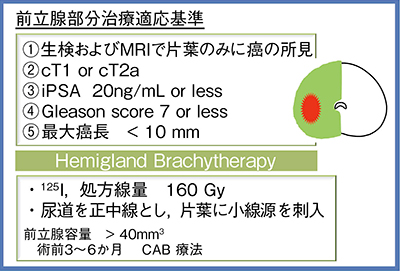

4.治療法

わが国において現実的に応用可能な治療法として,われわれは小線源治療を行っている。国際的なコンセンサスミーティングにて,小線源治療を用いたFocal therapyの報告も出てきており,ある程度の方向性も示されている。

当科では2010年から前立腺の片葉小線源治療を行ってきた。適応基準および治療法を図3に示す。対象症例は,年齢の中央値が71歳,リスク分類はlowが12名,intermediateが11名の計23名である。術後のPSA値は全例で改善しており,Phoenix定義に基づく生化学的再発は全例において認めていない(図4)。排尿機能は術後早期に一過性の増悪があるが,1年ほどで治療前のレベルに回復。性機能も治療前後でほとんど変化は認めず,治療前に良好な機能を示す症例では,射精を含めた全性機能が温存された。

図3 前立腺片葉小線源療法の適応基準と治療法